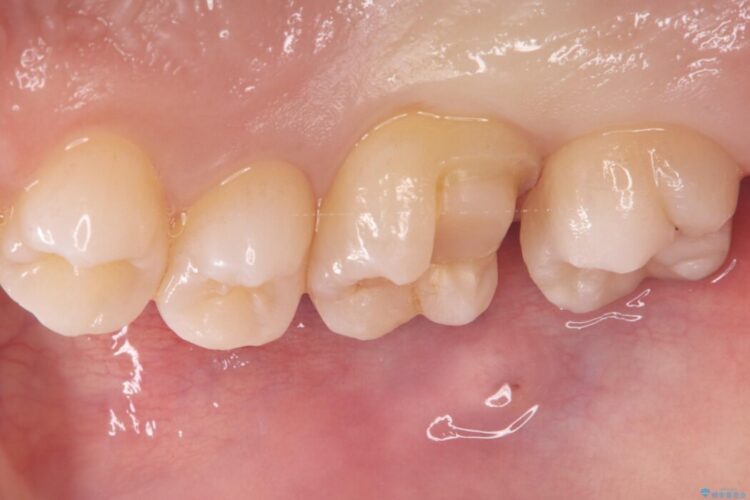

治療後について

セラミックアンレーセット時は、ラバーダム防湿を行っています。